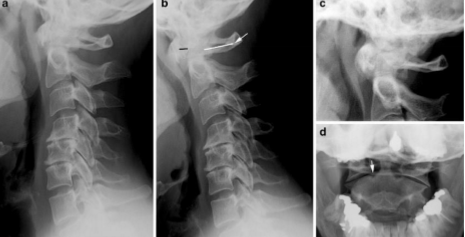

radiology - rheumatoid arthritis

can widen the predentate space in the cervical spine

can lead to fusion of the posterior elements in the cervical spine